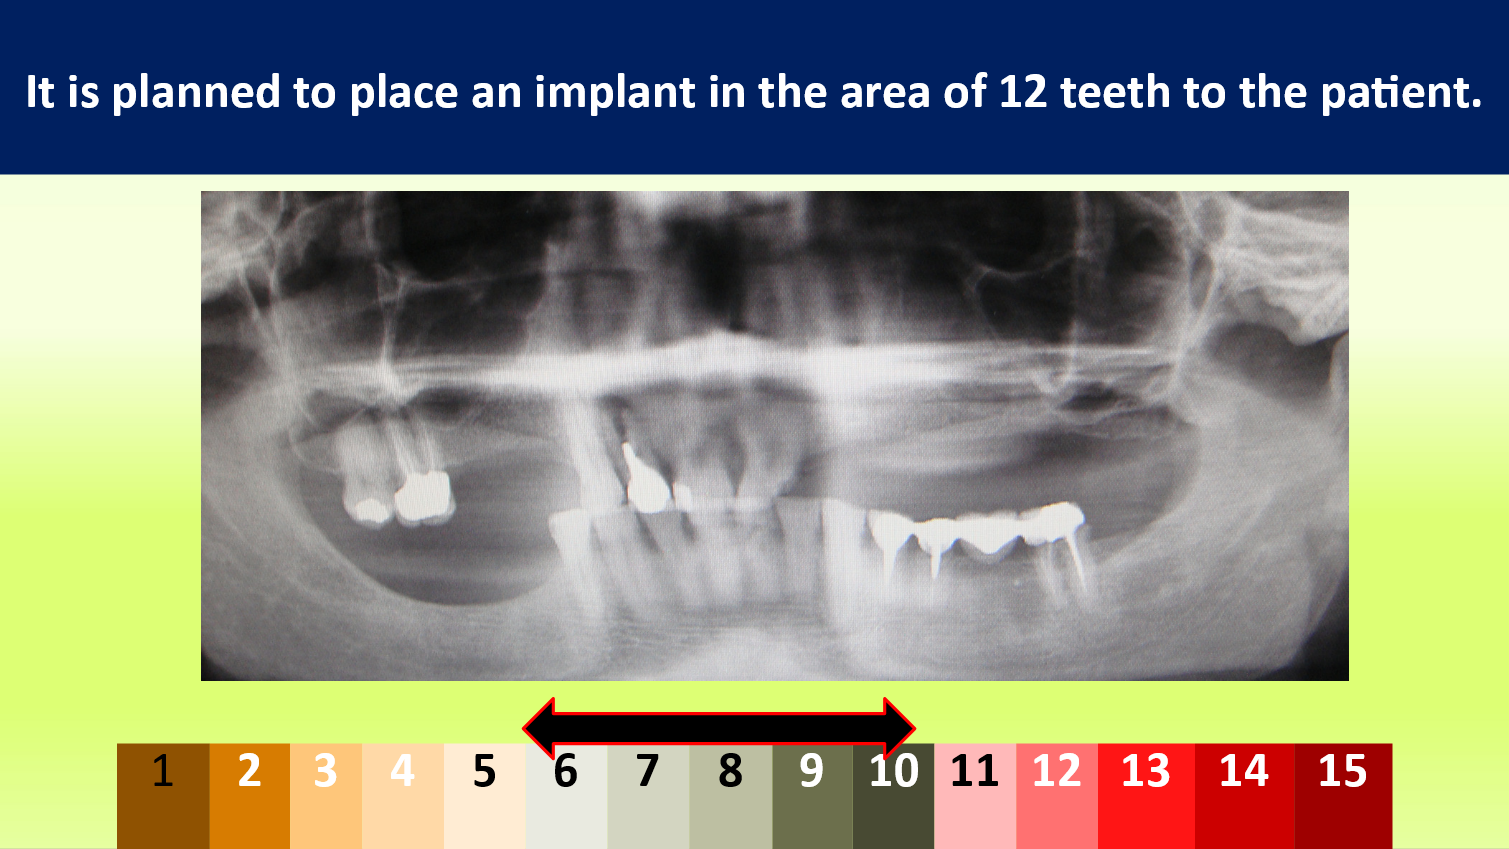

Case 12

“Vector” Implant placement in the area of 22 and 12 missing teeth is the only correct solution.